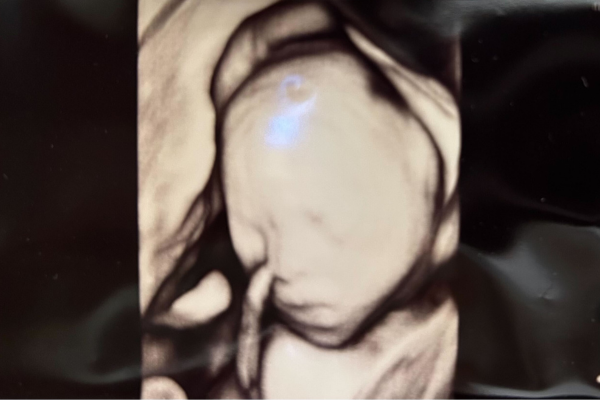

Gravid uge 21

Uge 21+0 – 21+6

Din baby måler cirka 26 cm, og vejer nu omkring 400 gram. Barnet kan registrere berøring igennem livmodervæggen. Mange babyer bevæger sig lidt ekstra under scanning eller når der lyttes hjertelyd med elektrisk doptone. Barnet vil have vågne perioder og søvnperioder. Det er i denne uge 2. trimester scanningen skal laves.